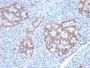

Applikationen IHC

IHC, FFPE (verified)

Positive Control

Jurkat cells. Small Intestine or Pancreas.

Antibody target cellular localization

Nucleus

IHC (FFPE) (verified)